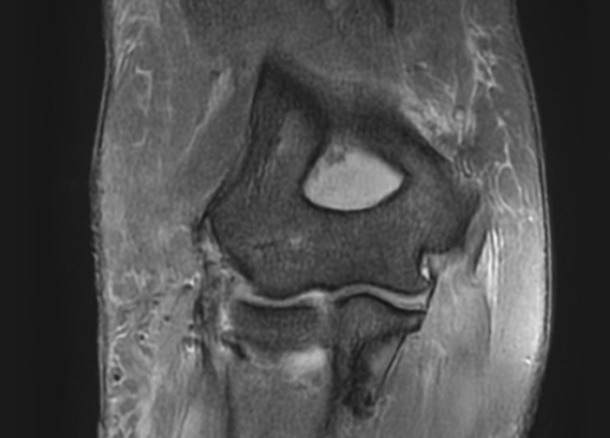

Before 수술 전